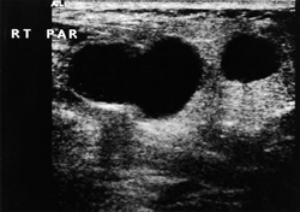

Najčešći uzrok uvećanja žlijezde slinovnice u bolesnika zaraženih HIV-om je solitarna ili multicentrična benigna epitelijalna cista. Njezina etiologija je još uvijek nejasna, a patogeneza kontroverzna (3). Navodi se uloga epidermotropnih virusa kao što je Epstein Barr Virus (EBV) i Cytomegalovirus (CMV). Definira se kao cista unutar parotidnog limfnog čvora najčešće u infraaurikularnom dijelu žlijezde. Limfoidna proliferacija može rezultirati u duktalnoj opstrukciji i dilataciji (5). Poznat je i entitet nazvan „Sindrom difuzne infiltrativne CD8 limfocitoze“ karakteriziran bilateralnim otokom parotida, difuznom infiltracijom CD8 limfocita, osobito u plućima i cervikalnom limfadenopatijom (3). Ultrazvučnim pregledom uočava se spektar nalaza: od pojedinačnih, jednostavnih, oštro ograničenih anehogenih cisti u jednoj ili obje parotide, do brojnih cisti od kojih neke mogu biti septirane ili sadržavati interni detritus (Slika 3.) (5). Uporabom linearnih sondi visoke frekvencije prikazujemo cistu u žlijezdi slinovnici, a ujedno nam služi i za navođenu dijagnostičku citološku punkciju.

Slika 3.: Ultrazvučni prikaz limfoepitelijalne ciste parotidne žlijezde s internim detritusom